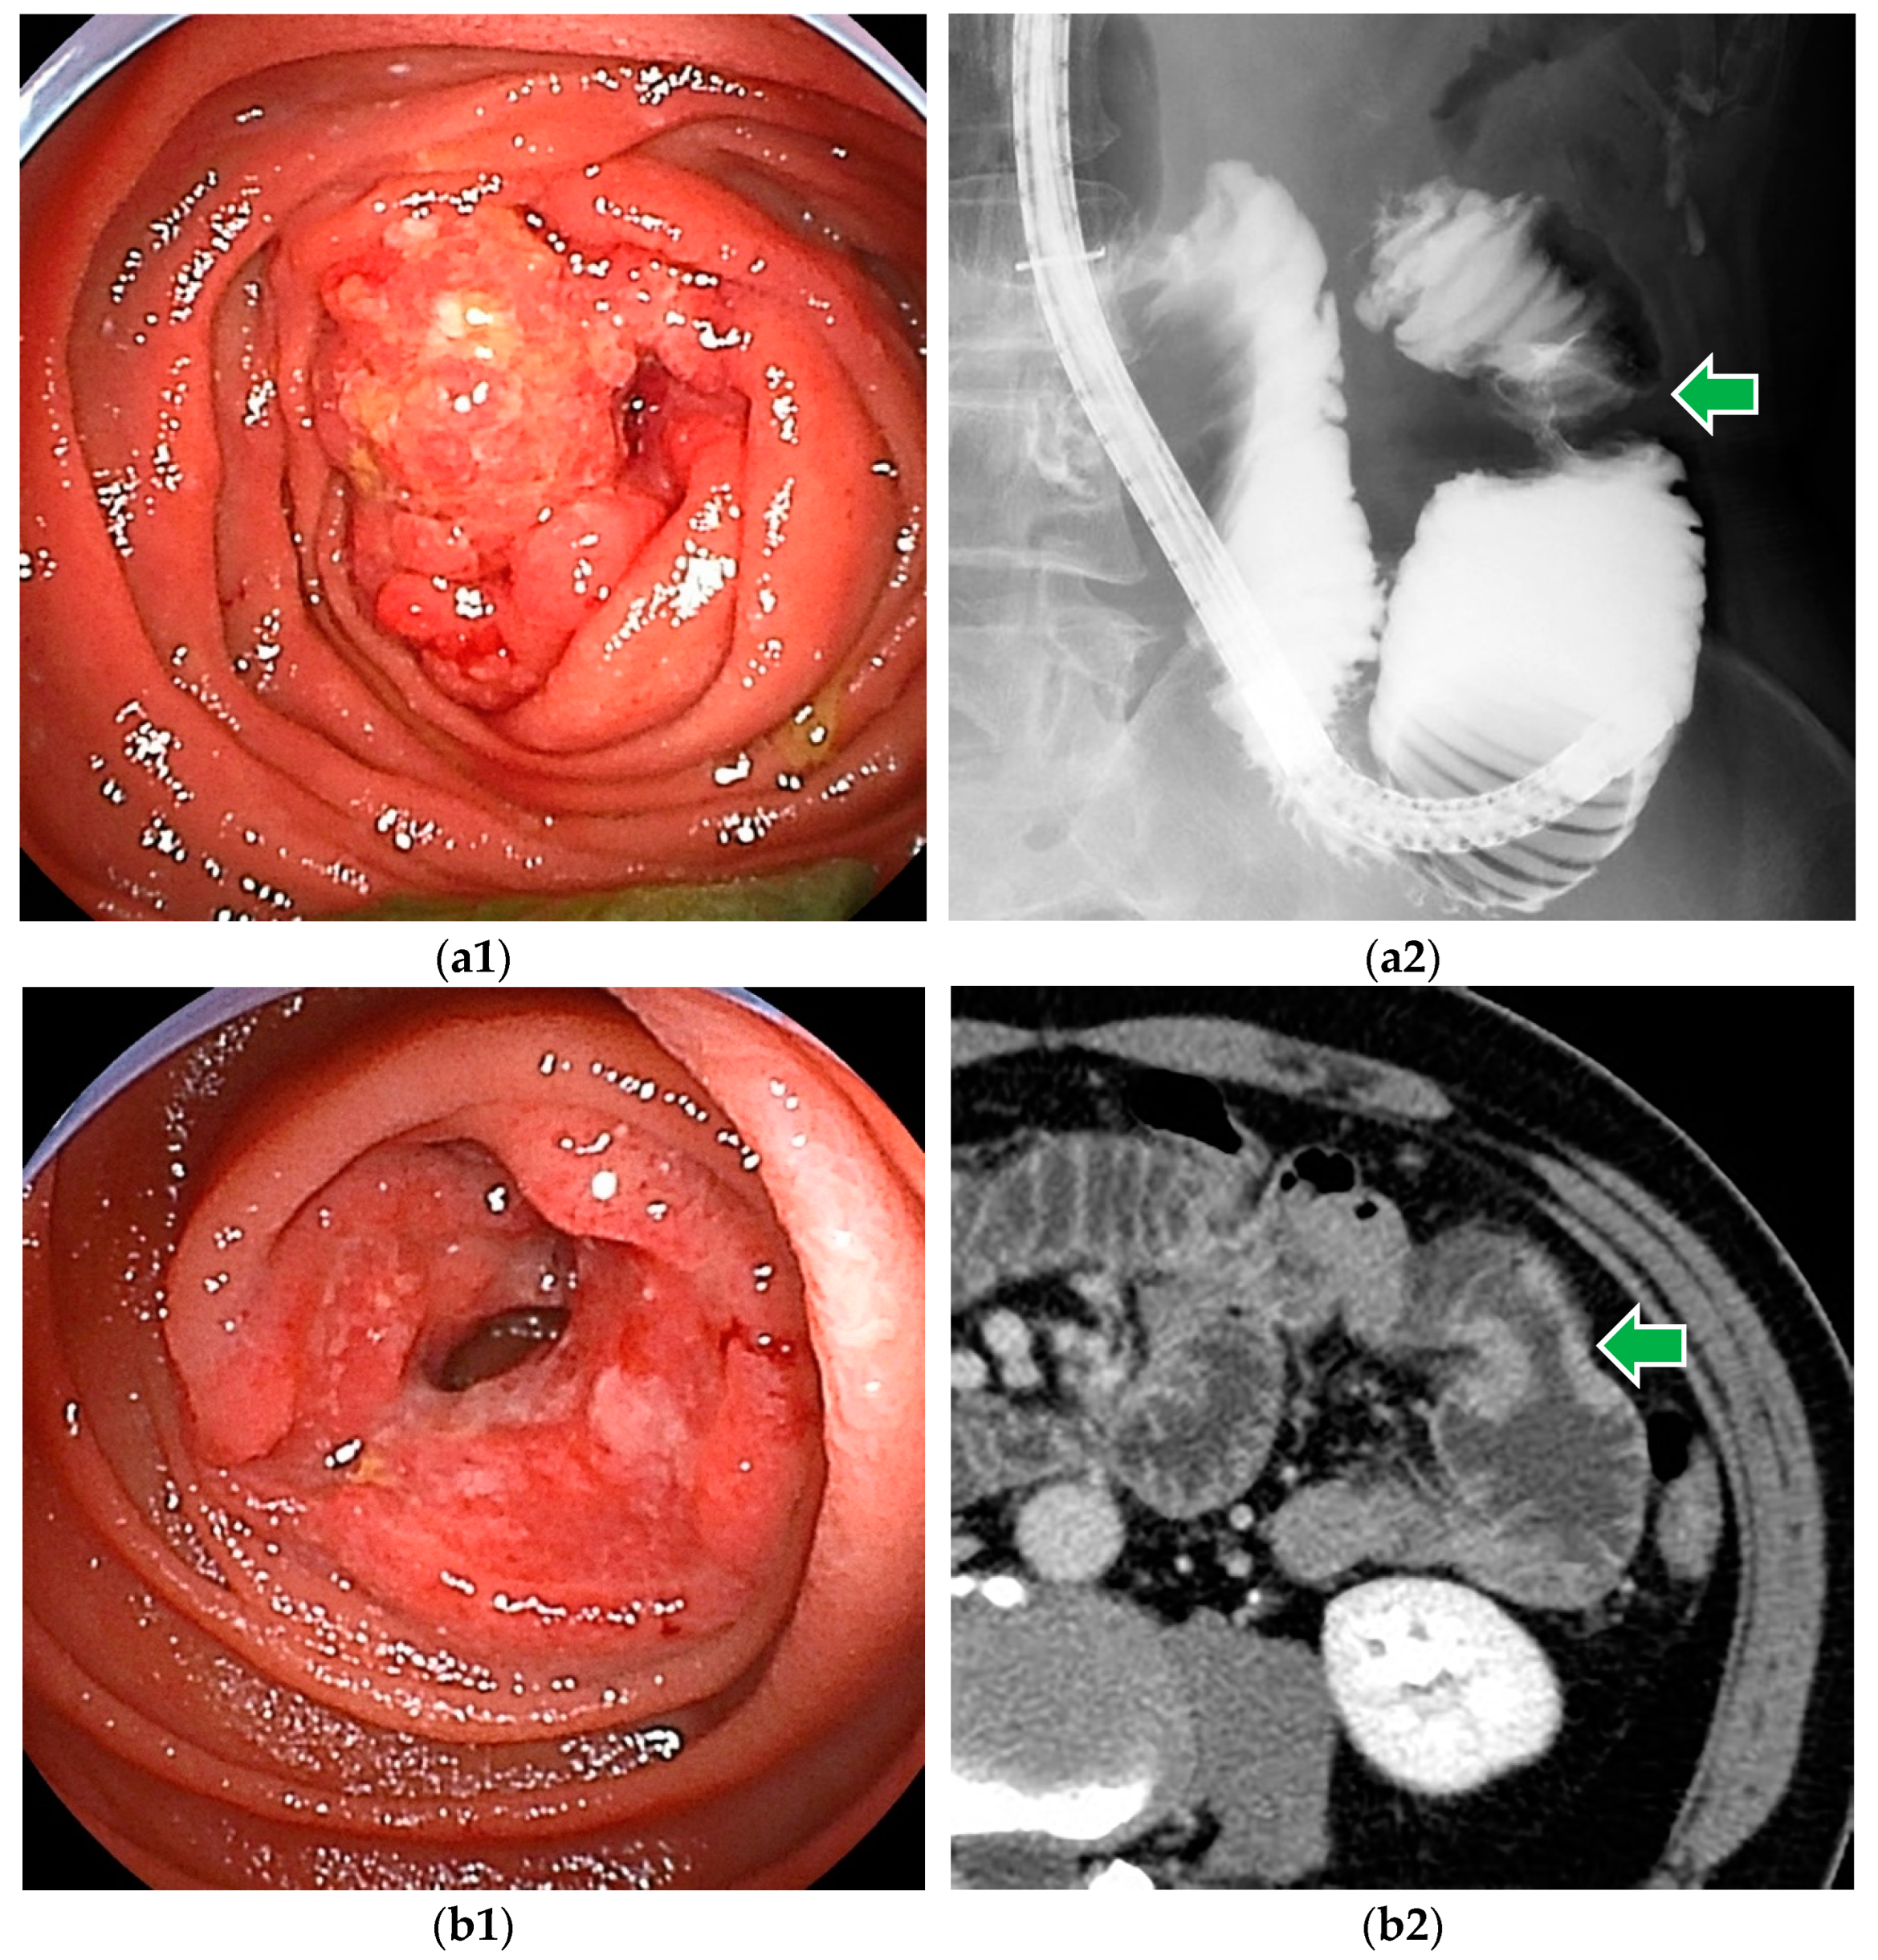

6.1. Small Bowel Adenocarcinoma

6.2. Gastrointestinal Stromal Tumor

6.3. Malignant Lymphoma

6.4. Neuroendocrine Tumor